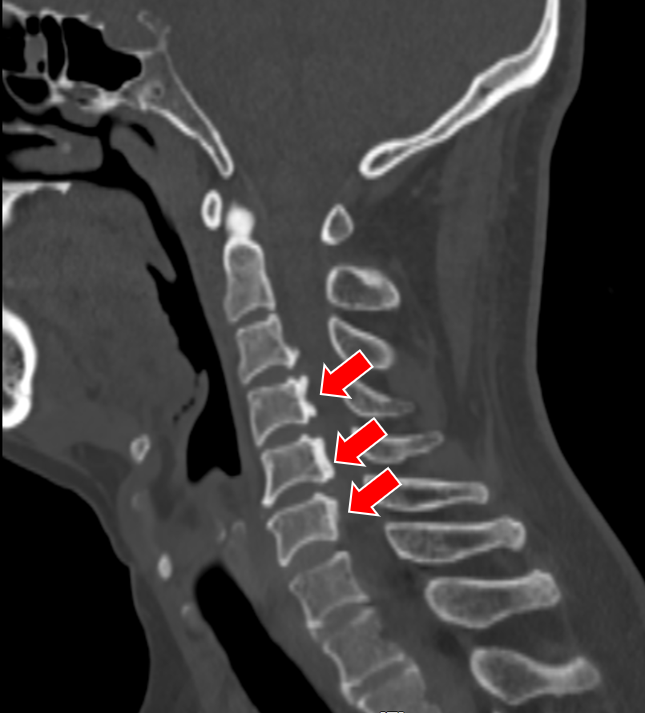

就在吕飞出院的当天,另一位症状相似的脊髓型颈椎病患者吕艳也来办理了住院手续。原来她是吕飞的亲姐姐,今年46岁。姐弟俩的症状和影像学表现都几乎相同,可见颈椎后纵韧带骨化确有一定的家族遗传倾向。吕艳告诉我们,他们姐弟这些年看过不少医生,都建议尽早手术,但因为听说颈椎手术风险极高,所以一直都选择“拖字诀”处理。这次吕飞的手术效果,给了她极大的信心和勇气,她毫不犹豫地也选择来做手术。

(姐姐的颈椎CT显示她的颈椎椎体同样存在明显的后纵韧带骨化,与弟弟不同的是,她的韧带骨化程度更严重)

(吕姐的接受的手术与吕弟一样,C3~6椎管扩大成形术。)